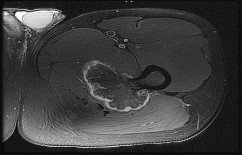

Question 7

A 15-year-old male presents with knee pain, and biopsy confirms conventional high-grade osteosarcoma of the distal femur.

Following neoadjuvant chemotherapy and wide resection, what histologic finding represents the most significant prognostic factor for long-term survival in localized disease?

Explanation

In localized high-grade osteosarcoma, the degree of tumor necrosis after induction (neoadjuvant) chemotherapy is one of the most powerful prognostic indicators. A "good response" is typically defined as ≥ 90% necrosis (Huvos grade III or IV). A necrosis rate of less than 90% is an adverse prognostic factor for survival.